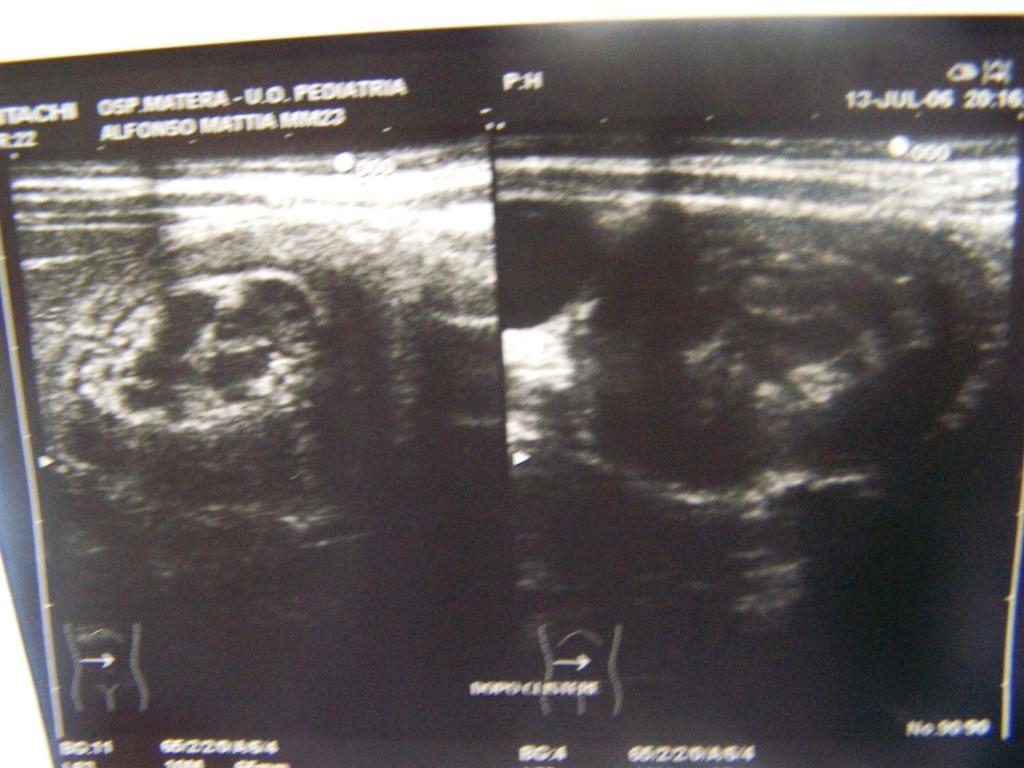

Il quadro ecografico dopo il clisma si modifica un poco (riduzione dell�asse maggiore della massa e comparsa di minima quantit� di liquido nel suo contesto) (Figura 2a). Il segnale doppler � ben apprezzabile (Figura 2b).

Figura 2 (a). Quadro ecografico dopo clisma a bassa pressione di sol. fisiologica calda.